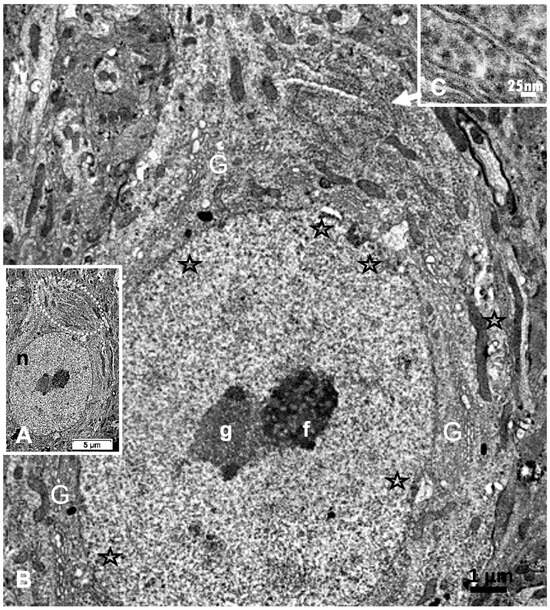

Reviewing micrographs obtained from past data of ODS along with these observations, the murine CNS thalamic region investigated at the time lapse ODS12h can be exemplified where an approximate surrounded and underlined part corresponded with that part which underwent demyelination, as shown in Figure 8A. There, an ODS core area with wasted neuropils showing among its spongy landscape aspect can be seen. In the immediate outskirts, some neurons can be found with LM (Figure 8B) and parts of them were still recognized with TEM (Figure 8C). As shown, in this latter micrograph, two adjacent ODS core neurons demonstrated their necrotic deterioration due to irreversible injury, as their heavily damaged morphology demonstrated nuclei that underwent chromatolysis, revealed by diluted chromatin or remnants whose nucleoli had vanished leaving vacuolated neuroplasms. There, a loosened endoplasm, and several lysosomal and lipofuscin bodies remained. Additionally, when a satellite oligodendrocyte was still recognized, it was as a shrunk, lytic deteriorated body that bore a compacted necrotic nucleus. Within 100–150 µm, the distance away from the worst core damage of the ODS epicenter made of deteriorated neuropils, some of the nerve cell bodies displayed resilience by showing remaining funnel-shaped to elongated shaft-shaped projections issued from their perikaryal zones and, in the best findings we were able to observe, extensions ranging from 2.5 to 15 µm in length (Figure 6, Figure 8, Figure 9, Figure 10, Figure 11, Figure 12, Figure 13 and Figure 14), also evidenced by the ARL13B labeling (Figure 3, Figure 4, Figure 6A, Figure 13A and Figure 14A). At first, micrographs collected with TEM showed numerous granules in these extension that corresponded with the high ribonucleoprotein content associated or not with elongated cisterns of endoplasmic reticulum reaching the core of these axon extensions and, while reaching the funnel constriction segment, the heavily proteinaceous content revealed numerous paraxial and parallel neurotubules (Figure 8D,E). An enlarged view in Figure 9 seems to carry the fine structure aspect of this growth extension of the axon hillock, known as the axon initial segment (AIS) where innumerable proteinaceous components, including neurotubules and associated cytoskeletal macromolecules, appear arranged in periodic rows along and perpendicular to or encircling the cylindric AIS shape and neurolemma can be viewed. The neuroplasm itself, with an enlarged view (Figure 9 insert), can show an underlined parallel concentration of particulate proteins that could be called a sub-neurolemmal structure, further suggesting the unique and crowded peculiar architectural cytoskeletal components necessitated to construct and grow this special segment of the nerve cell body extensions.

2.5. ARL13B Label in ODS48h: LM and TEM: A Primary Cilium Emergence

The thalamic neurons located adjacent but at less than 100 µm distal from the necrotic core ODS, as seen in Figure 8A–E, and more clearly in Figure 9, can be recognized from their shape, using LM, as a large pale nucleus with indent(s) that reveal an evident stained nucleolus and, with TEM, the same highly contrasted, large nucleolus shows large amounts of accumulated granular transcripts (as granular component) accompanying the dense and fine fibrillar components of the chromatin distributed throughout the very active nucleoplasm (Figure 9A, Figure 10A, Figure 11A and Figure A2). At first glimpse, the adjacent neuropil and the satellite oligodendrocytes appear typically located attached to neurons as satellites but, with TEM scrutiny, these were mostly damaged by ODS cell stress and are surrounded by large neuropil intercellular spaces throughout and possess other cells’ and myelin remnants, implicated after leakage of blood fluids, plasma with serum, contributed via the small regional necrotic cells to the archetypal term of ‘liquefaction necrosis’. However, within this ODS damaged zone outskirts, among some degraded and corpses of neuropil, resilient neurons found in the outskirt region were marked by large euchromatic nuclei and active nucleolus; they showed numerous ribonucleoproteins but also reveal through their fine structure that they possess delicate but clear-cut primary cilia (Figure 10A,B). Each cilium length ranged from 4.5 to 6.0 µm long and width from 0.2 to 0.25 µm that is filled with a core of granular cytoplasm and microtubules. The example illustrated shows its transition zone cell attachment consisting of a narrow transition segment or ‘neck’ of about 0.15 µm in width, that is tied by basal fibrillar materials, and forms a ciliary pocket or cove-like space of the plasma membrane. Within the neuroplasm, obscured by numerous ribosomes, a microtubule fascicle and other subcellular filaments can be barely seen originating from the adjacent perikaryal region and reaching the basal side of the primary cilium whose random sections constitute a sort of ‘hub’ region, probably endowed by a centriolar piece structure in some other ultrathin section. In Figure 10A–C, adjacent to the primary cilium, one can note filopodia-like extensions, as these could also be relevant to this rejuvenated change associated with cell resilience (Figure 10C). Other neurons of the same region (Figure 8D,E), at low magnification, bear an axon hillock that becomes like a funnel, similar to the neurons, and more distally located away from the core ODS damages, as shown in Figure 11, Figure 12, Figure 13, Figure 14 and Figure A2, displaying axon hillocks and an axon initial segment without any ciliation. Underlined by ocher yellow (Figure 12A) and enlarged in Figure 12B, the Golgi apparatus saccules characteristically erupt in numerous small vesicles (50–70 nm diam) that accompany ribonucleoprotein particles (mainly RNAs), revealing swirled ribbons of polysomes in places. Vesicles and particles appear to redistribute into the AIS, showing as an initial squeezed cylindric shape aligning the entered neurotubules into a paraxial to parallel orientation congested by one or more long, twisted mitochondrion. Both mitochondria profiles and inner neurolemma leaflet can be decorated by small round to elongated vesicles while the outer leaflet has typically no myelin. However, some synaptic contacts are noted amongst end-feet profiles of astrocytes, recognized by their highly contrasted granules of glycogen content (Figure 12A,B).